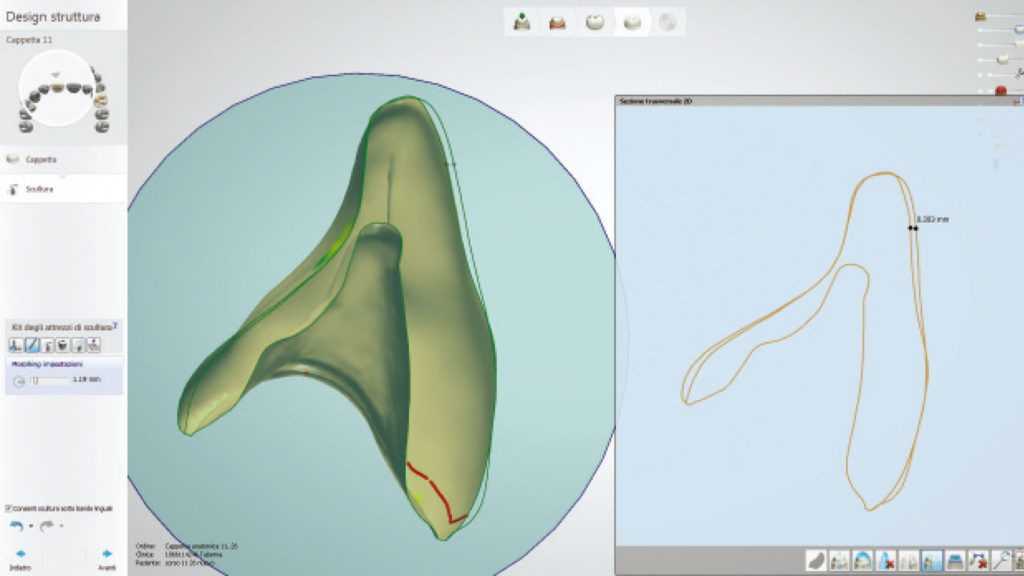

Für diesen Fall ist es von grundlegender Bedeutung, die vom Zahnarzt generierten Pfeiler, so exakt wie möglich zu replizieren, weshalb wir uns für den digitalen Weg entschieden haben (Abb. 27a und b).

In der Software können wir uns im Schnittbild die verfügbare Dicke der zukünftigen Kronen anzeigen lassen, woraus sich wichtige Schlüsse über die mechanische Festigkeit der Versorgung ableiten lassen (Abb. 28). Die Farbanalyse hat zudem ergeben, dass keine komplizierten internen Charakteristika reproduziert werden müssen, und ein ästhetisches Ergebnis leicht zu erreichen ist.